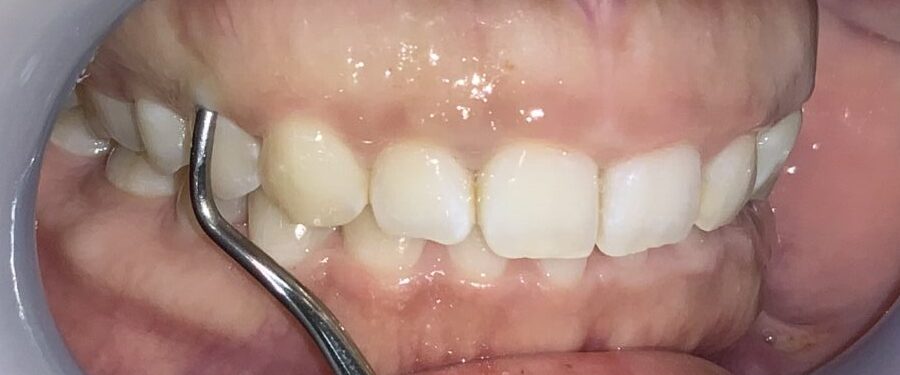

この歯は犬歯です。犬歯もたくさんの歯ぐきに覆われているようですが、治療をする場合には注意が必要です。

犬歯はあまり大きくすると、八重歯のように見えてしまい、せっかくの治療が台無しになる場合があります。また、被っている歯ぐきがたくさんあっても、歯ぐきが薄い場合があり、このような歯ぐきの場合は、治療後に歯ぐきが退縮してしまい、歯槽膿漏の歯ぐきのように見えてしまう場合があります。

難関の犬歯を超えたところで、第一小臼歯の4番面の歯を検査します。

奥歯なのに、歯ぐきがたくさん被っているようです。3番目の犬歯と違い、奥歯の形になってきている4番目の歯は、犬歯とは違う注意が必要です。

この歯は奥歯の形なので、歯ぐきを取りすぎると、知覚過敏になる場合があります。また、前歯と奥歯の間の歯ですから、前歯に比べて治りが遅い傾向にあります。歯ぐきの切除も慎重に行わなければなりません。